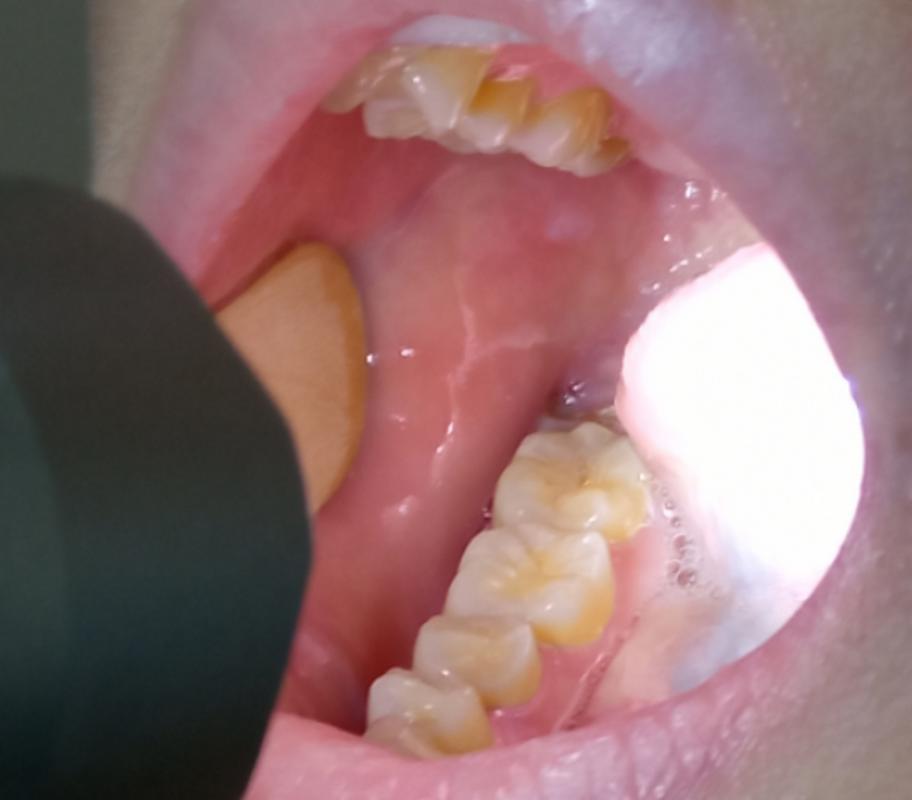

口腔白色黏膜是何原因?

为了帮助您更好地理解,我将这些原因分为三大类:生理性/良性、炎症性、癌前/恶性病变。

炎症性或感染性原因(需要关注和治疗)

这类情况通常伴有不适、疼痛或灼热感,需要明确病因并进行治疗。

口腔念珠菌病(俗称“鹅口疮”或“雪口病”)

- 表现:最典型的表现是口腔黏膜上覆盖着一层白色、奶油状、不易擦掉的斑点或斑块,强行剥离后,下方会发红、糜烂,甚至有轻微出血,常见于舌、颊、上颚等部位,常见于婴幼儿、老年人、免疫力低下者或长期使用抗生素/激素的人群。

- 原因:由真菌(白色念珠菌)过度生长引起。

- 处理:需要就医,医生通常会开具抗真菌药物(如制霉菌素、氟康唑等)。

口腔扁平苔藓

(图片来源网络,侵删)- 表现:一种常见的慢性炎症性疾病,表现为白色、灰白色的条纹、网状或斑块状病损,可发生在口腔黏膜的任何部位,常见于颊黏膜,病损周围黏膜可能正常或发红,患者常感到口腔粗糙、烧灼感,有时伴有疼痛,部分病损(特别是糜烂型)有癌变风险。

- 原因:病因尚不完全明确,可能与免疫、精神压力、药物、感染等多种因素有关。

- 处理:需要就医,治疗主要是缓解症状和控制炎症,使用糖皮质激素等药物,需要定期复查,监测癌变风险。

癌前病变或恶性病变(需要高度警惕并立即就医)

这类白色斑块通常是质地坚硬、不易擦除、长期不消且持续增大的。

白斑

- 表现:口腔黏膜上出现的不能被擦除的白色或灰白色斑块,质地较硬,表面可有皲裂或溃疡,无明显自觉症状,或仅有粗糙感。长期存在、持续增大的白斑,尤其是发生在舌缘、口底、颊黏膜等部位的,癌变风险较高。

- 原因:最主要的危险因素是吸烟(包括雪茄、烟斗)、嚼槟榔、酗酒。

- 处理:必须立即就医!医生会进行详细检查,必要时取一小块组织做病理活检(金标准),以排除癌前病变或口腔癌的可能性,治疗可能包括手术切除、药物等。